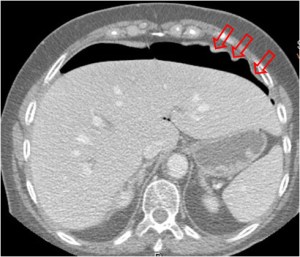

SIGNO DEL CUADRANTE SUPERIOR DERECHO

Signo de neumoperitoneo en la radiografía simple de abdomen. Se aprecia una colección aérea lineal (como la que marcan las flechas rojas en la imagen) o triangular que se dispone de inferolateral a superomedial. Si es triangular, la colección aérea presenta una morfología cóncava superolateralmente (ver Signo del Duce). Se cree que las colecciones lineales representan gas en el espacio subhepático derecho mientras que las triangulares reflejan la presencia de gas a nivel del receso posterior del espacio subhepático (saco de Morison).

La imagen corresponde a una perforación duodenal en el transcurso de una CPRE con papilotomía, de ahí la presencia de contraste en la vía biliar y en el duodeno (flecha negra).